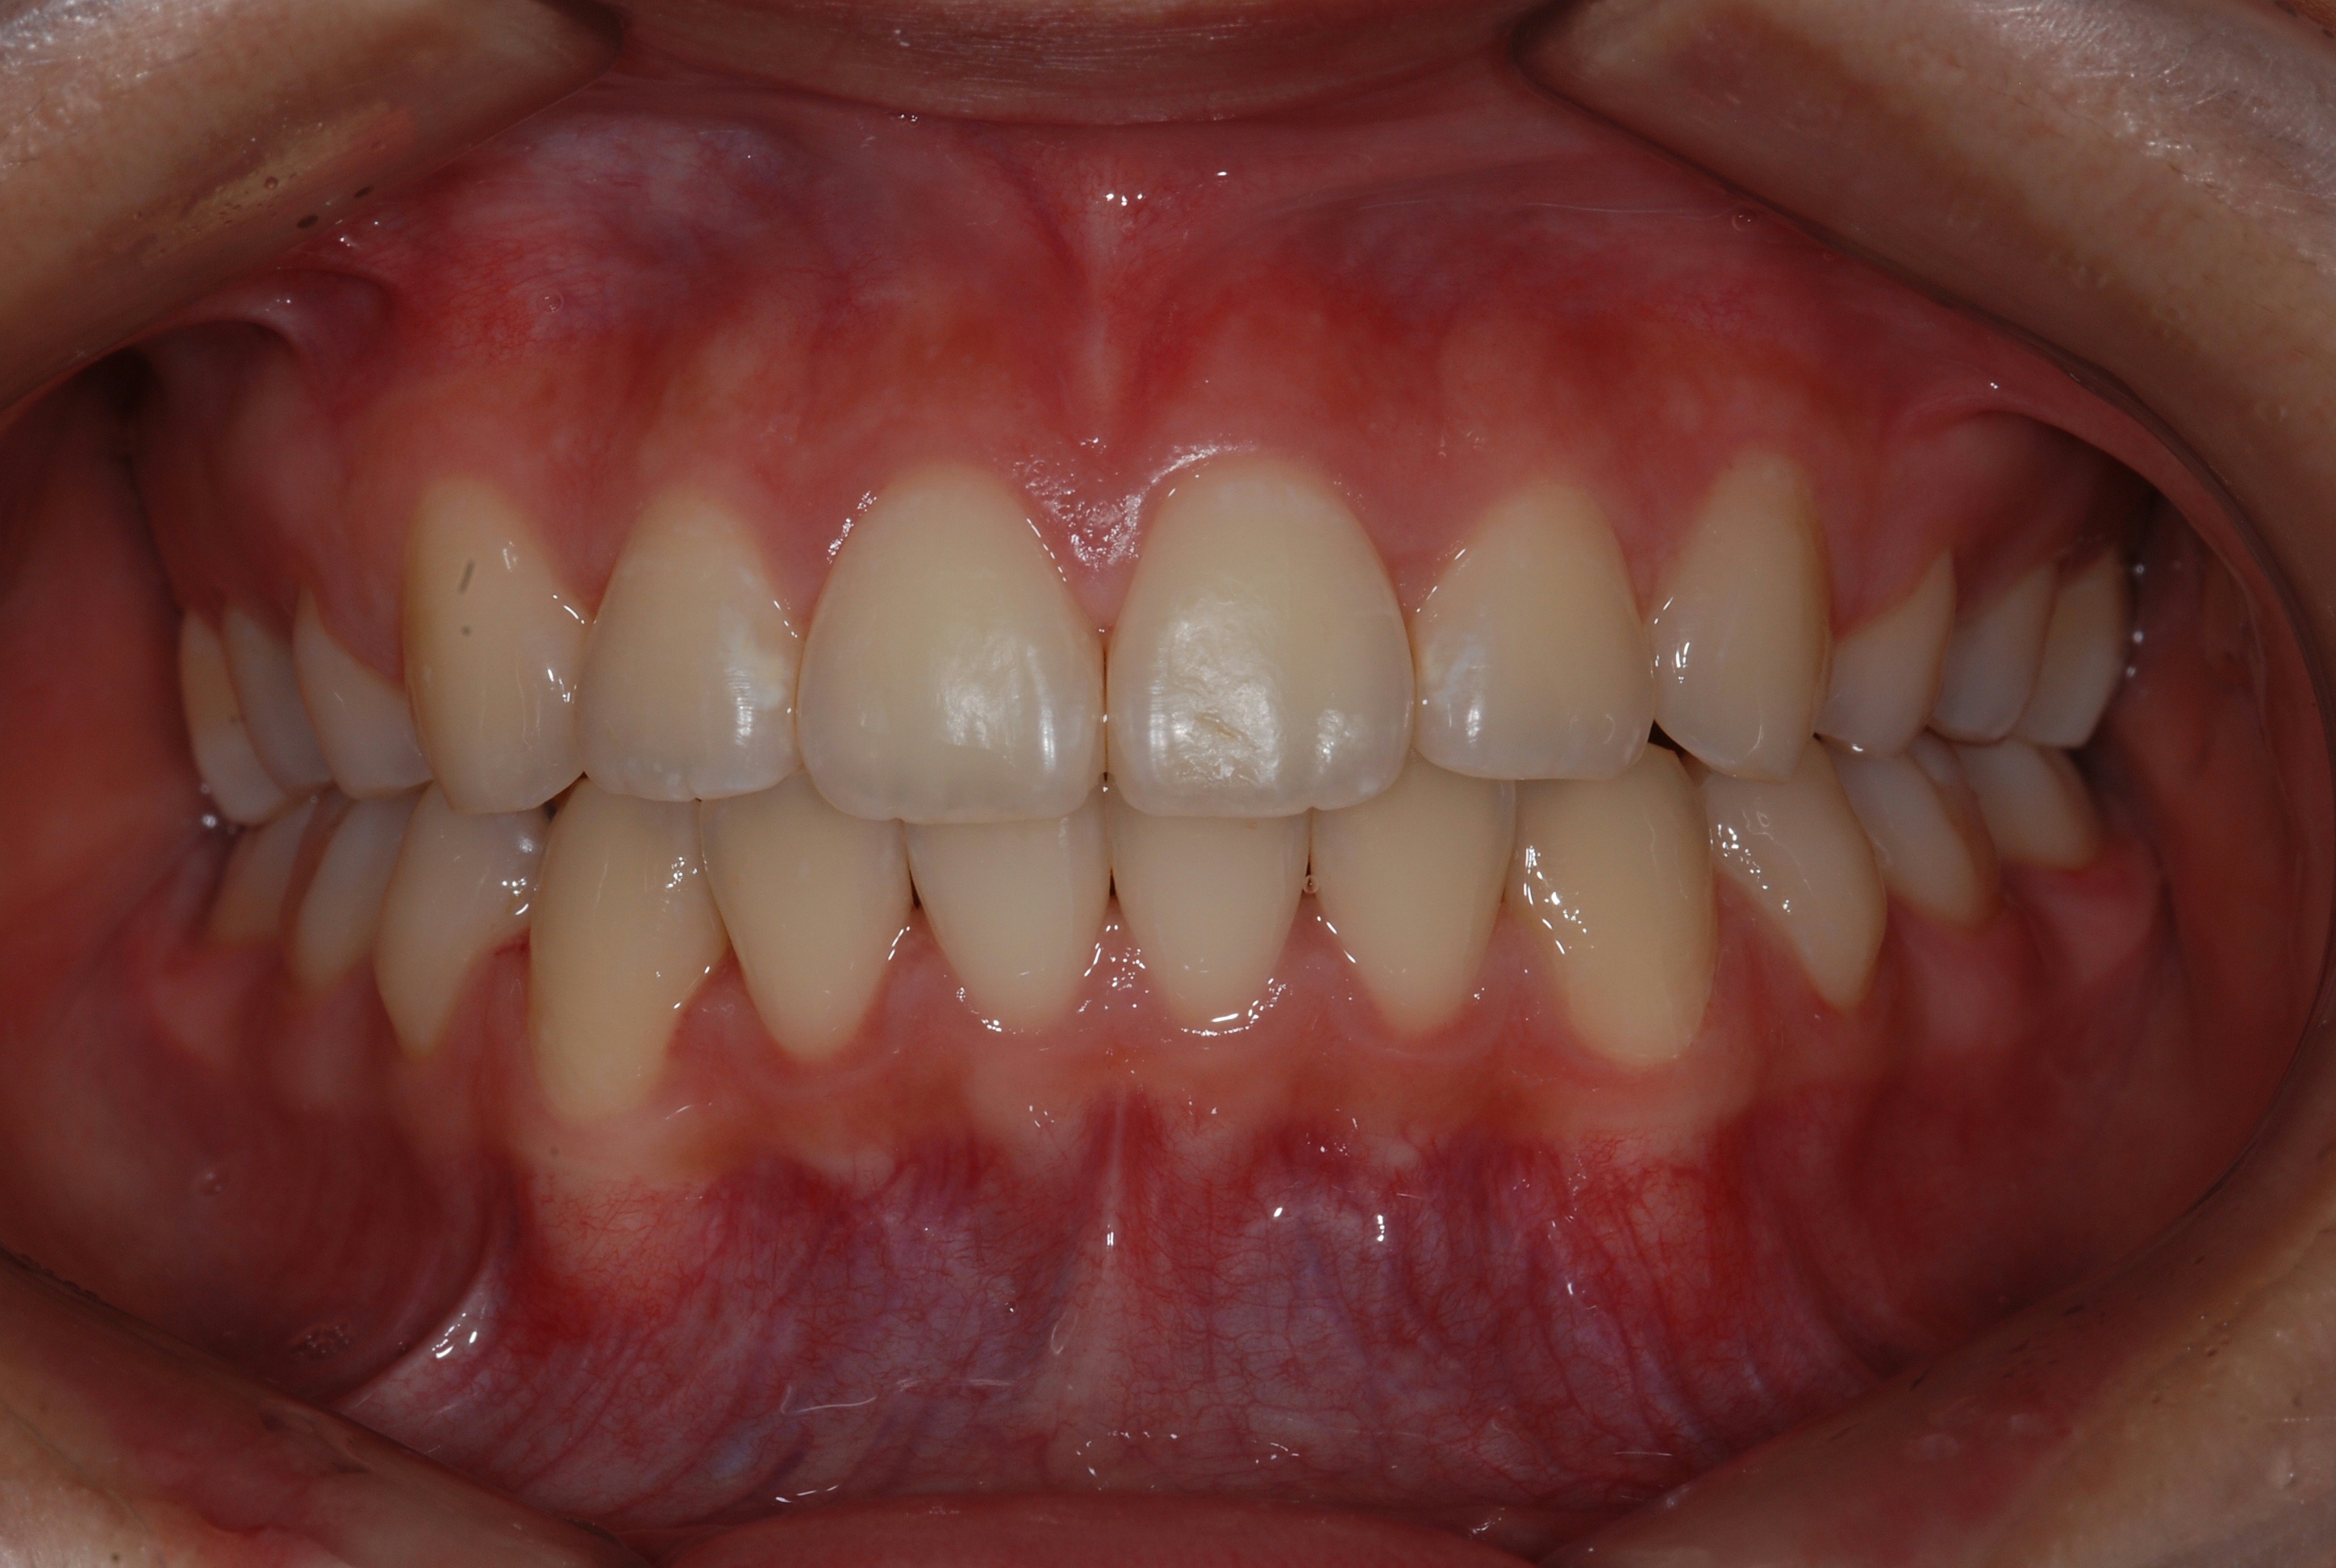

치료 후 사진입니다.